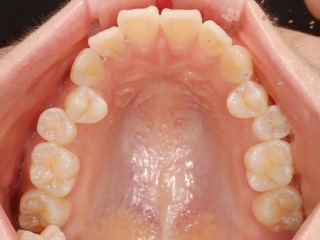

치아공간 사이가 좁아 덧니가 심하게 발생한 증례 .

3D 스캐너를 이용하여 치아구조를